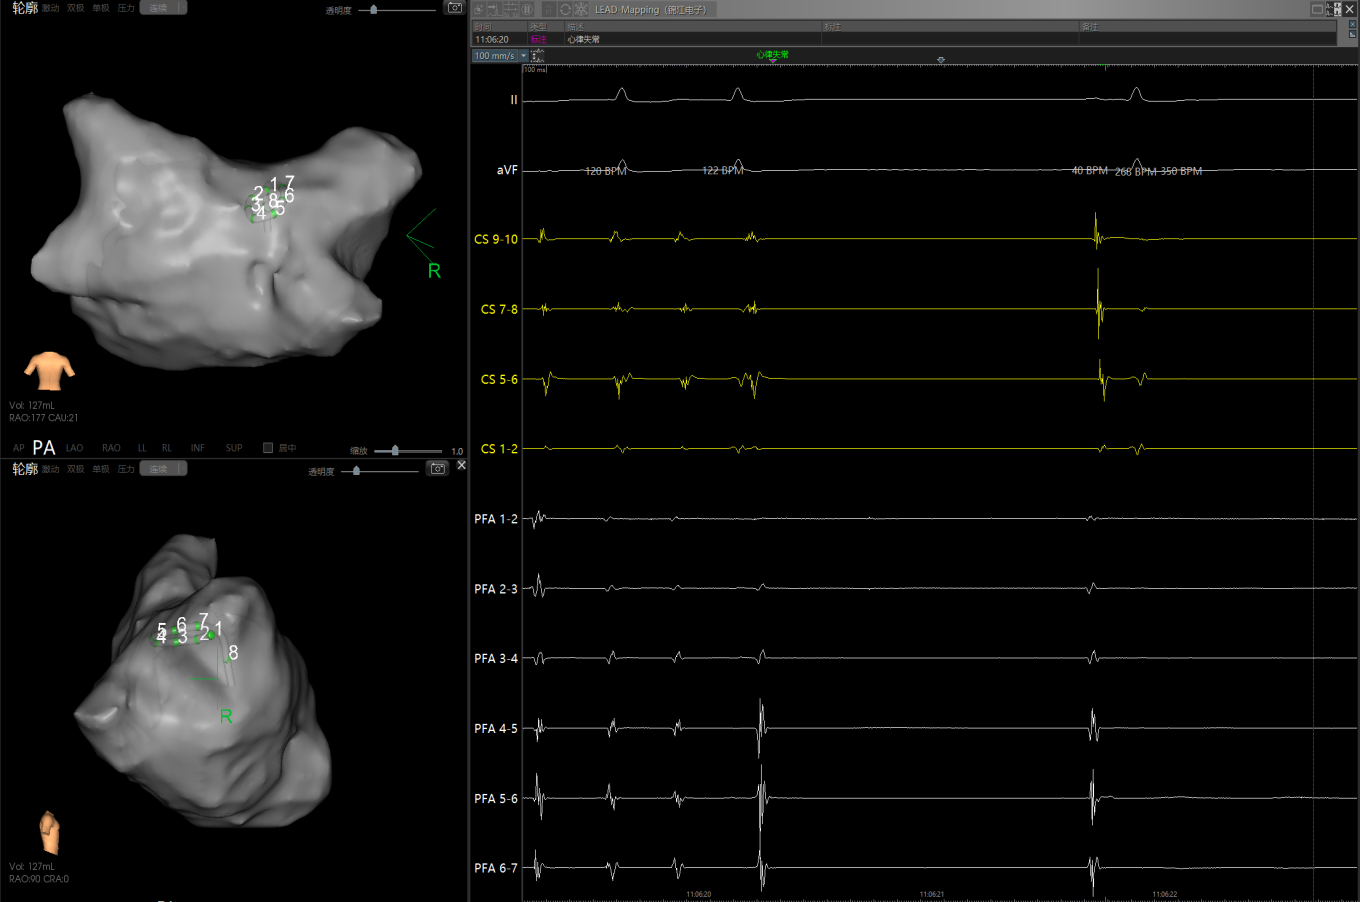

经充分术前评估及准备后,该患者手术在抗心衰药物持续静脉泵入、高流量吸氧支持下及麻醉、护理团队的通力配合下进行,由薛建颖、崔明亮主治医师具体实施。术中通过右侧股静脉送入心腔内超声至右心房,排除左房血栓后成功指导房间隔穿刺,沿可调弯鞘管送入锦江心脏脉冲电场消融导管至左房,构建左房三维解剖模型并行基质标测,标测显示左房基质差,分别行左侧、右侧肺静脉及后壁BOX消融。消融参数:1800v,400ms,400μs,共放电消融140次(消融右肺静脉时转复为窦性心律),验证双肺静脉均隔离。术后重新标测显示所有肺静脉均已急性阻滞,消融效果理想,肺静脉前庭损伤范围也达到了预期的标准,同时心腔内超声监测未见明显心包积液。手术仅用时30分钟,时间明显缩短,手术过程精准高效。术后患者恢复情况良好,维持窦性心律。

图3 PFA于右肺静脉后壁交叉消融时转为窦率,继续消融